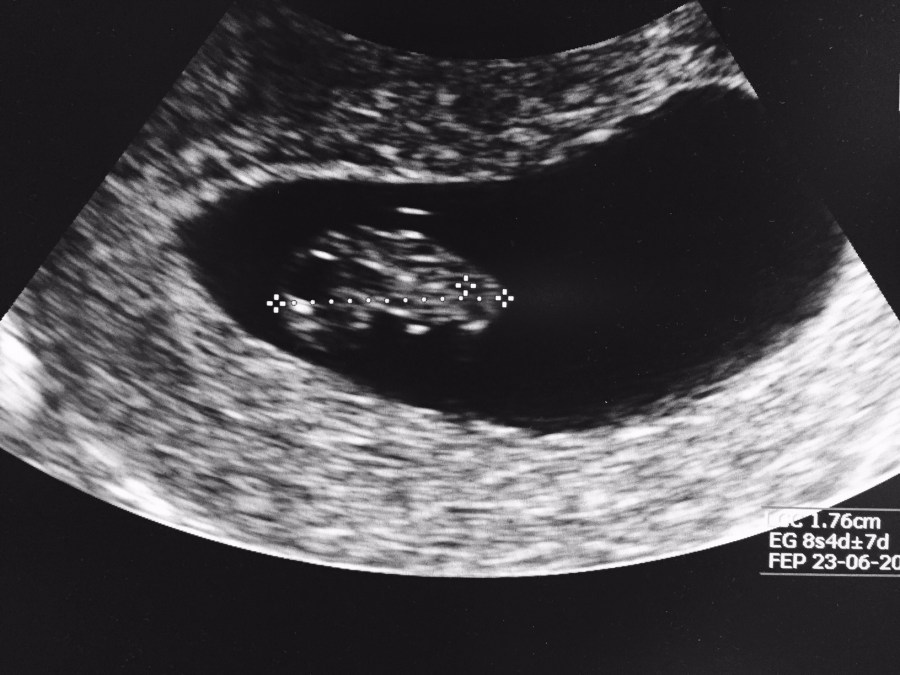

El primer eco… la cédula de tu bebé!

Una norma, entre nosotras las mujeres, ante prueba de embarazo positiva, es que queremos salir corriendo a hacernos un eco! Antes de la 6ta semana, contadas a partir de la fecha de ultima regla, el eco no aporta mucha información y al contrario, puede generar stress/ansiedad, mientras que el eco realizado entre la 6ta y… Continúa leyendo El primer eco… la cédula de tu bebé!